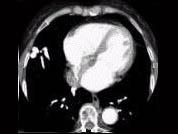

请看一组肺血管的CT增强图像,考虑最可能的诊断为 ( )A、肺动脉钙化B、肺动脉破裂C、肺动脉狭窄D、肺动脉扩张E、肺动静脉畸形

问题 请看一组肺血管的CT增强图像,考虑最可能的诊断为 ( )

选项 A、肺动脉钙化 B、肺动脉破裂 C、肺动脉狭窄 D、肺动脉扩张 E、肺动静脉畸形

答案 E